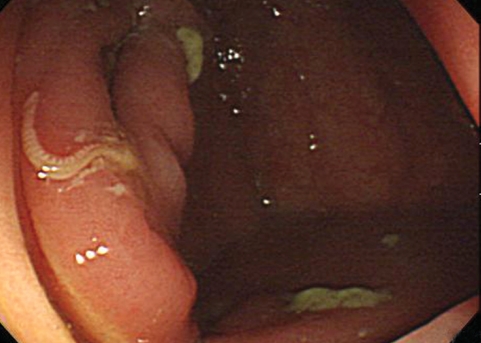

He was found to have a small, white worm on the proximal ascending colon during colonoscopy. One end of the parasite was embedded in relatively normal colonic mucosa and the other end was coiled and movable (Fig. 2). The parasite was removed by forceps. Microscopic examination of the retrieved parasite was consistent with T. trichiura, which was thought to be a male worm. It had a thread-like head portion and a coiled thicker portion. He was treated with albendazole.